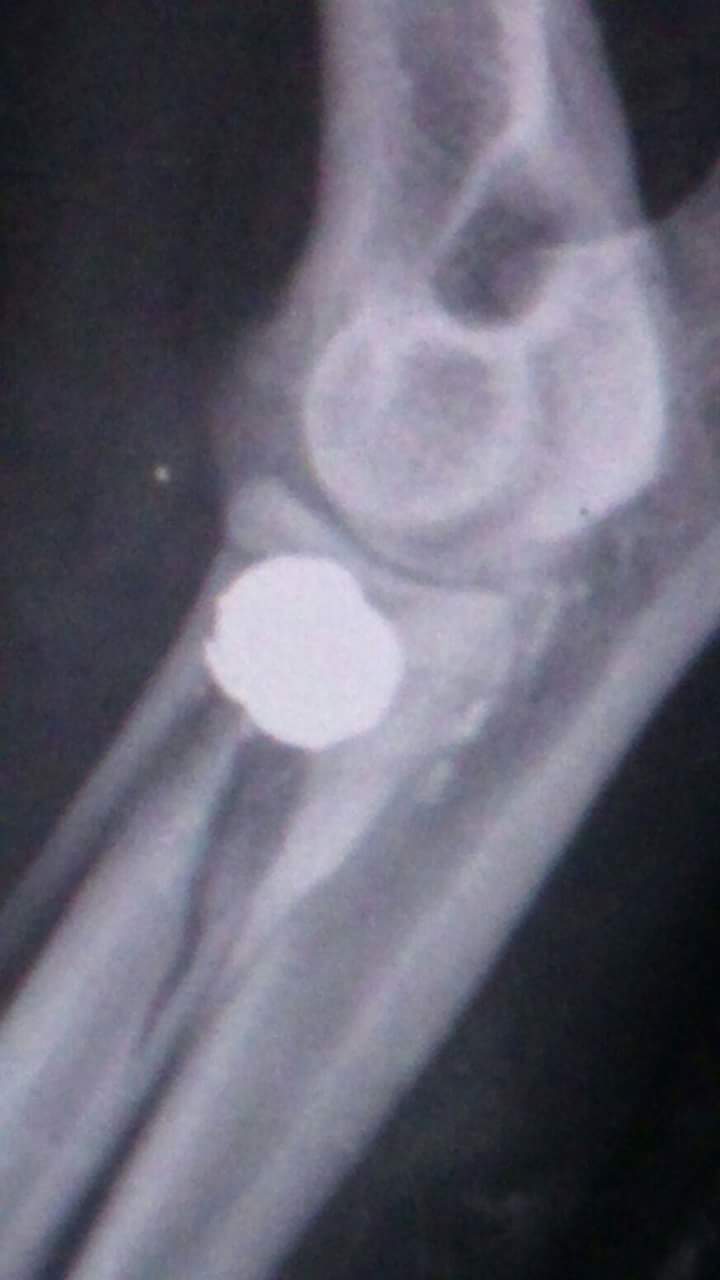

Snoopy es uno de esos perros. Llevaba ya muchos días abandonado, porque el estado en el que lo encontramos era lamentable. Deshidratado, desnutrido, con el pelo largo, enmarañado y lleno de porquería y barro. Además, vimos que cojeaba y pensamos que lo habían atropellado. Nada de eso. Por si no fuera bastante con dejarlo tirado a su suerte, Snoopy recibió un disparo en una pata y tenía el hueso completamente destrozado y soldado alrededor del proyectil. No sabemos cuánto tiempo llevaba así, pero seguro que mucho. No sabemos cuantísimo dolor tuvo que pasar malviviendo en el monte con un disparo. Pensamos que su patita quedaría inútil, ya que del dolor no podía ni rozar el suelo. Se operó y aunque el veterinario nos decía que Snoopy iba a tener cojera crónica… nada de eso. Se recuperó al 100% porque tenía unas ganas inmensas de jugar, correr… de vivir.